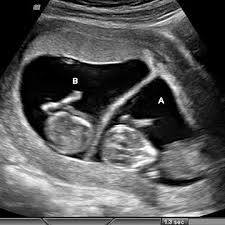

These facts are not only from over 10 years of experience being the #1 twin parenting website online, but some of the info is literally taken from our over 1 million parent audience. Their lungs are well developed by 34 weeks. Nevertheless, make the best of what you can and enjoy the luxury of pregnancy. From week 8 to 12, the last month representing the embryonic stage, your twins are swiftly progressing in their development they will have quadrupled in both length and weight. Twin pregnancy symptoms and conditions. Lowest prices from hundreds of sites all in one place. Your babies are approximately 7,5 cm (2.95 inches) from head to rump when you're 13 weeks pregnant with twins. 2697 grams / 5lbs, 15oz. Sep 26, 2018 · the second trimester is officially on once you are 13 weeks pregnant. The first trimester is the first three months or until 13 weeks pregnant with twins. When do you start showing with twins? The average newborn twin weighs 5 1/2 pounds. Your complete guide twin weight chart.

3261 grams / 7lbs, 3oz. Nevertheless, make the best of what you can and enjoy the luxury of pregnancy. How did you feel at 13 weeks? As well as the pregnancy symptoms being more severe, they can also occur much earlier on. All your children's organs are developed but are still maturing. Women who are carrying twins or multiples in their wombs tend to have it a tad more difficult than those who are pregnant with a single baby. From week 8 to 12, the last month representing the embryonic stage, your twins are swiftly progressing in their development they will have quadrupled in both length and weight. Estimated fetal weight for twins fetal growth chart fetal weight chart full term for twins twin fetal growth chart twin pregnancy week by week twin pregnancy: 2697 grams / 5lbs, 15oz. What would 13 weeks pregnant feel like? 3089 grams / 6lbs, 12oz. Sep 26, 2018 · the second trimester is officially on once you are 13 weeks pregnant. Twin pregnancy symptoms and conditions.